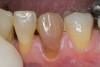

Figure 6  A single dark tooth from trauma needs to be examined carefully and evaluated with a radiograph. The safest approach is to bleach this tooth alone until the toothís response and maximum lightening can be determined.

Figure 6